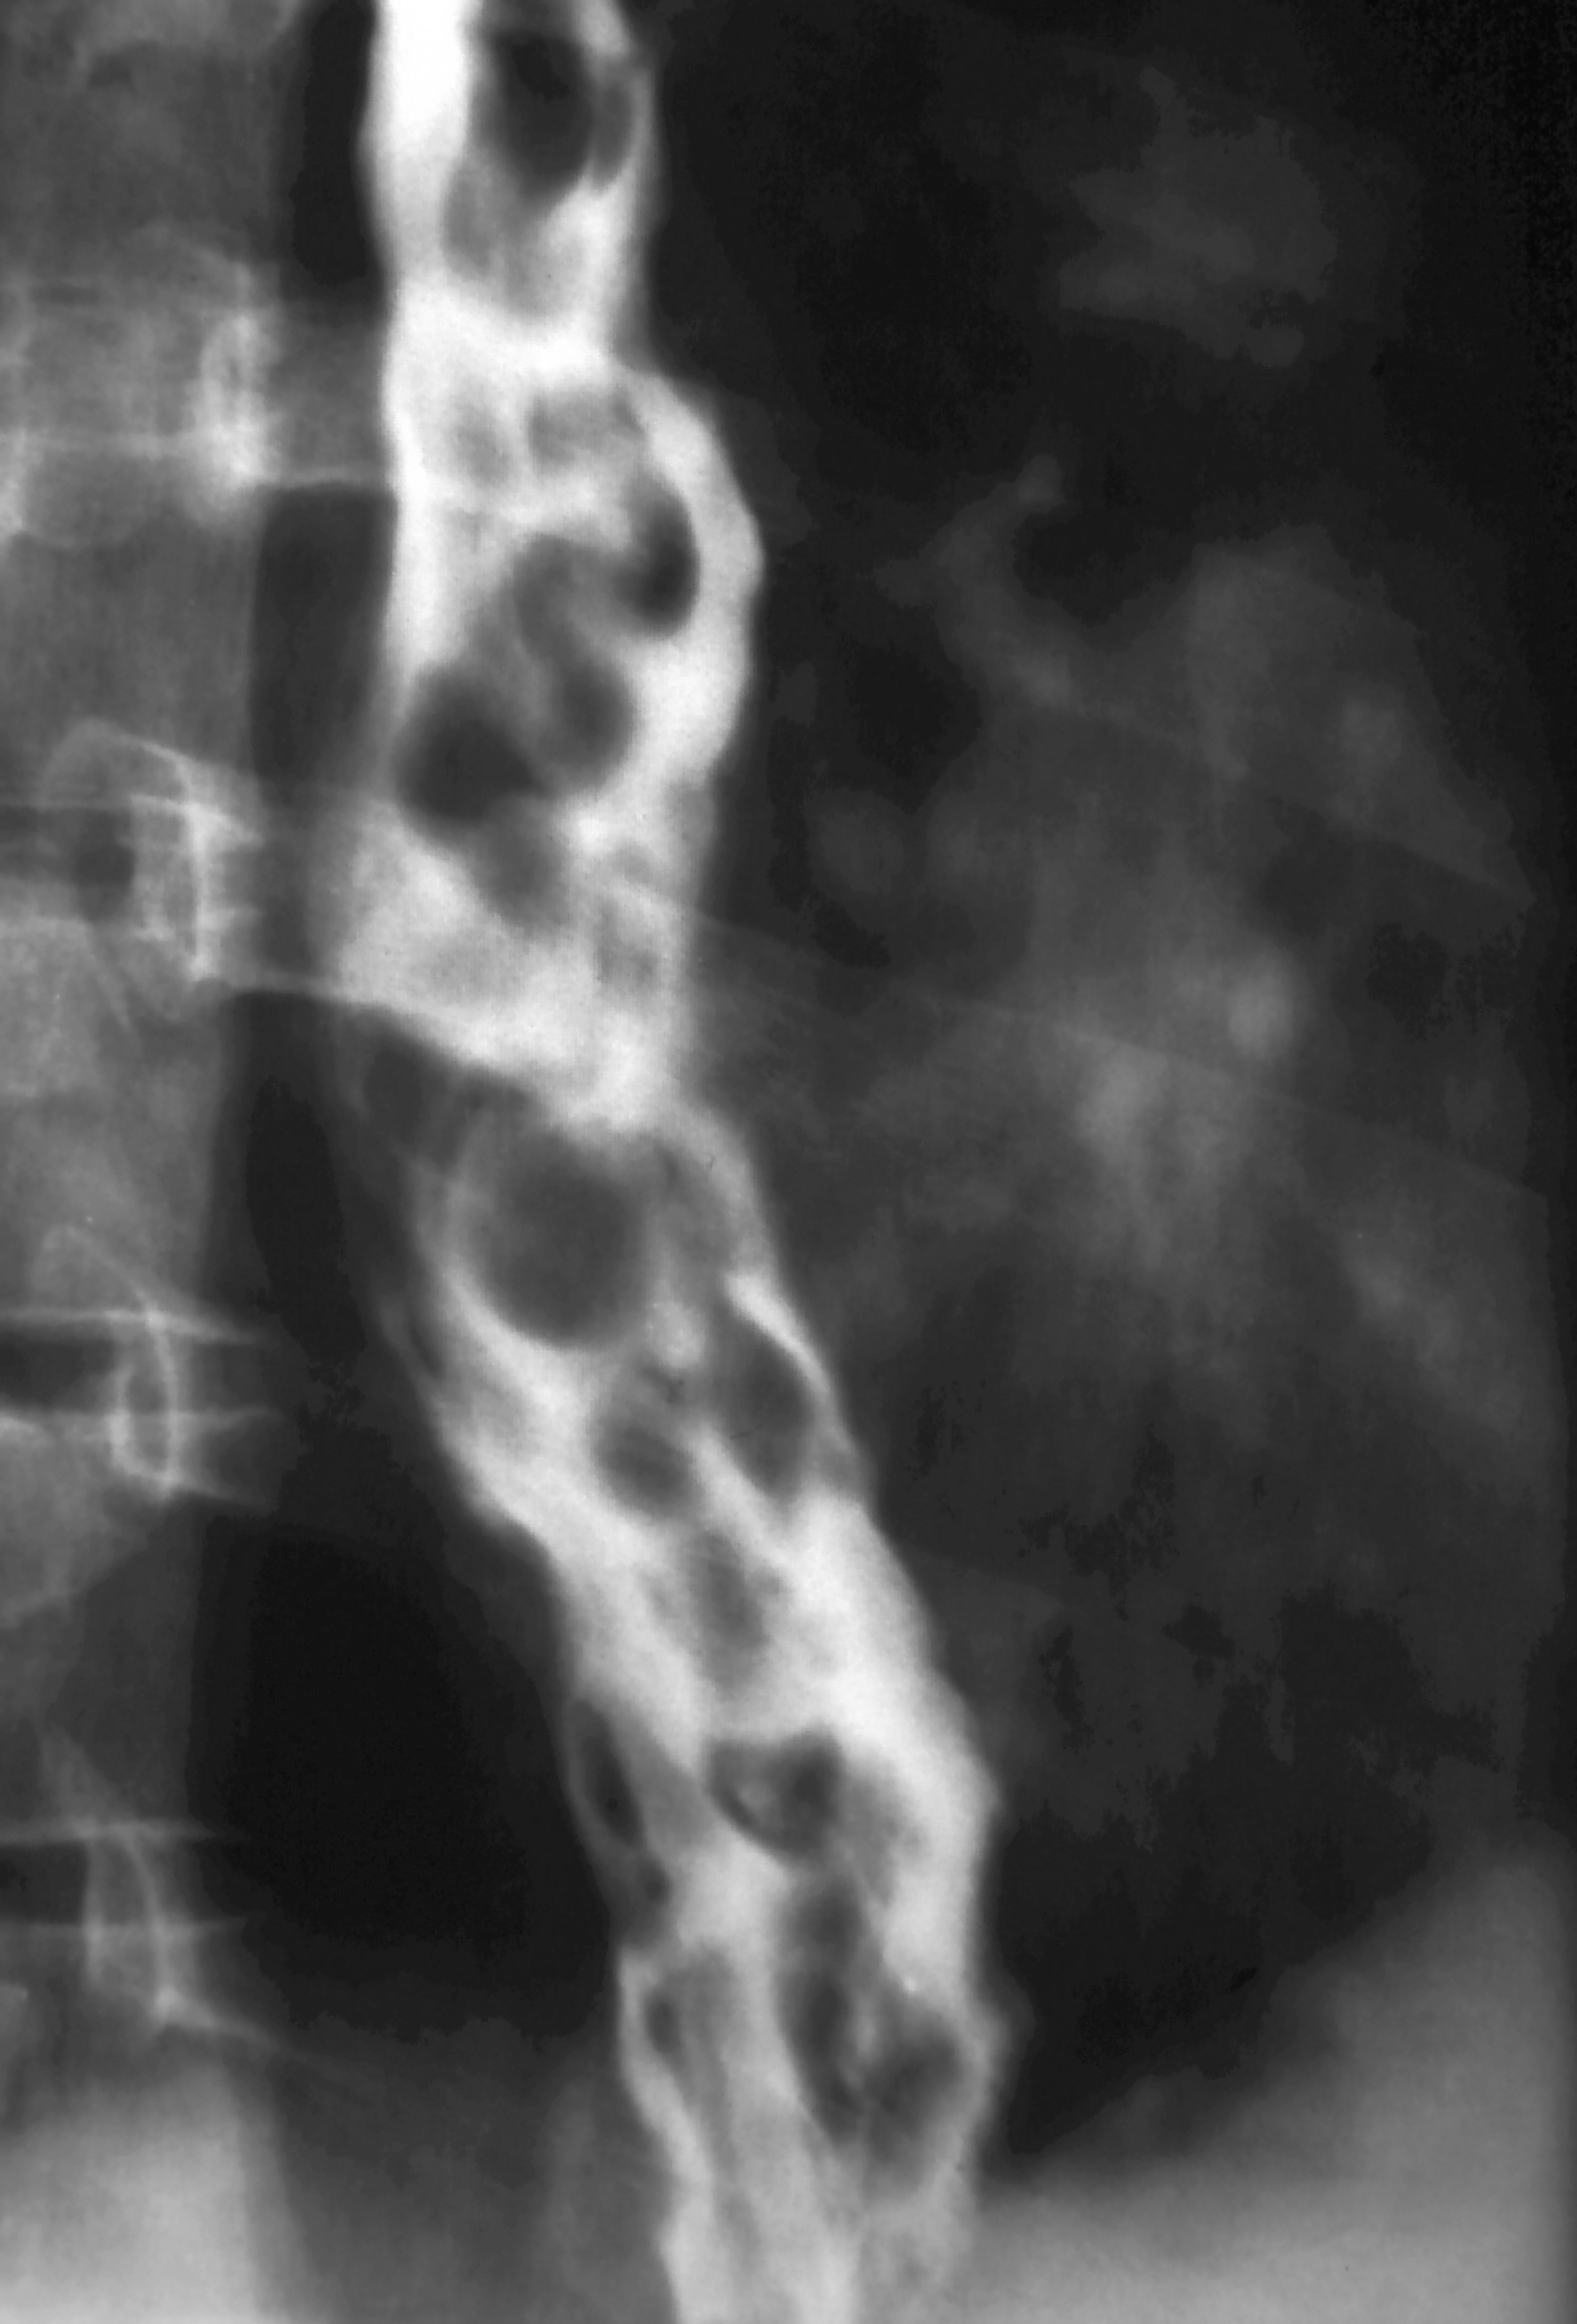

X-ray 폐고혈압으로 인한 뱀 모양의 식도 정맥류가 있는 사람의 엑스레이

바륨과 같은 조영제를 사용하여 식도를 촬영하면, 정맥류로 인해 부풀어 오른 식도 점막의 융기 등을 확인할 수 있다.